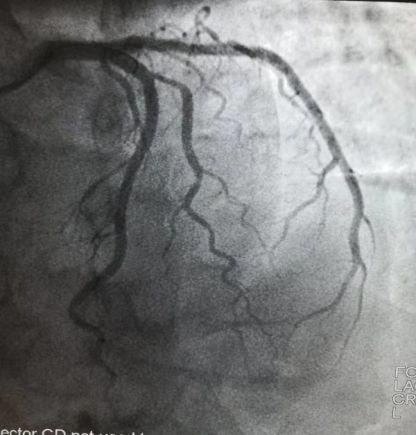

/术后血管通畅/

介于该患者介入术后监测血糖及糖化血红蛋白均较高,我们给予达格列净联合二甲双胍控制血糖,其余常规给予双联抗血小板、他汀稳定斑块、预防心室重构等药物治疗,现患者病情较平稳,血糖控制良好,已经康复出院。